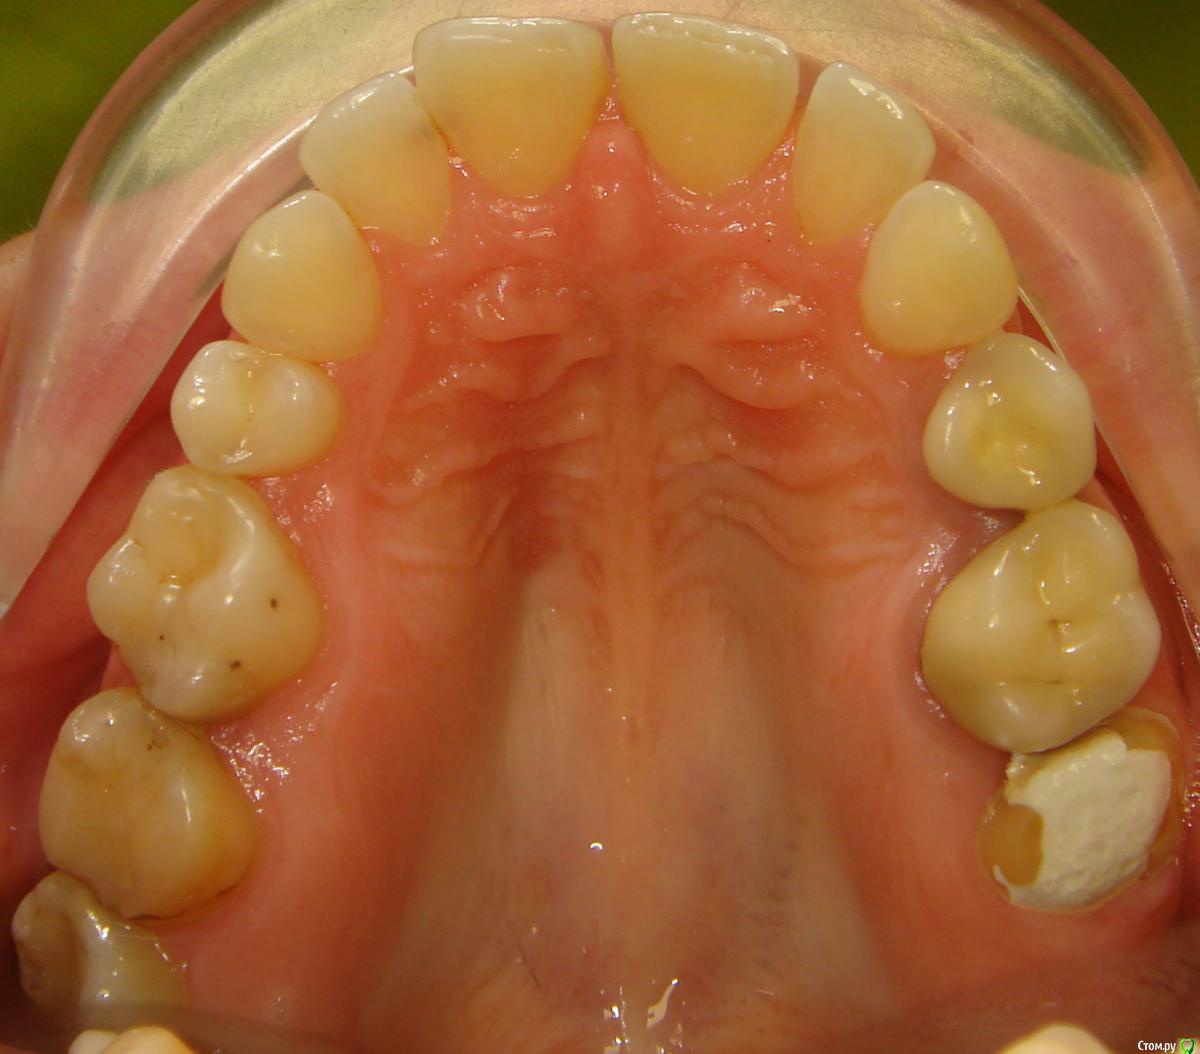

Opdihatop Опубликовано 16 апреля, 2017 Поделиться Опубликовано 16 апреля, 2017 Здравствуйте, коллеги! Что вы думаете по поводу этого случая? Объективно: вертикальный рост, первый костный класс. Незначительная протрузия резцов в/ч, нормальный наклон резцов н/ч. 15 зуб ретенирован. Значительное сужение в/ч, сужение н/ч.Вопросов 2: 1) Тянуть ли 15 зуб? 2) Планирую расширять при помощи SARPE, что делать с образовавшимся местом (которое и так сейчас уже есть)? Мне кажется такие большие реставрации будут некрасивыми. Ссылка на комментарий

Brigita Опубликовано 16 апреля, 2017 Поделиться Опубликовано 16 апреля, 2017 (изменено) Здравствуйте, коллеги! Что вы думаете по поводу этого случая? Объективно: вертикальный рост, первый костный класс. Незначительная протрузия резцов в/ч, нормальный наклон резцов н/ч. 15 зуб ретенирован. Значительное сужение в/ч, сужение н/ч.Вопросов 2: 1) Тянуть ли 15 зуб? 2) Планирую расширять при помощи SARPE, что делать с образовавшимся местом (которое и так сейчас уже есть)? Мне кажется такие большие реставрации будут некрасивыми.1) а куда его?2)Реставрации передних зубов имеется ввиду? Не такой большой промежуток, можно и реставрацию, если виниры не может позволить. расширение на SARPE - в таком возрасте без хирургии маловероятно, Вы же сами знаете, получите зубоальвеолярное небольшое расширение и наклон. Такой тонкий биотип, что там еще с кортикалкой будет. Мосты спаянные, вкладки. Чтобы узнать положение 5го надо КТ сделать, где у него корень - пойдет ли. Он видимо в небной костиА вообще - отдайте ее ортопедам. Она сама то что хочет? Изменено 16 апреля, 2017 пользователем Brigita Ссылка на комментарий

Brigita Опубликовано 16 апреля, 2017 Поделиться Опубликовано 16 апреля, 2017 Черные треугольники заполнить и рецессии убрать. я вот чего то не понимаю наверно.. где треугольники, которые она хочет убрать? я вижу диастему, трему 22-21, кариес 11-12, многочисленные рецессии, плохие ортопедические коронки, неправильно выполненные вкладки ( а может правильно? я не ортопед), скученность нижних зубов. А вообще вот интересно - в каком возрасте максимально возможно расширение на SARPE, у кого какой опыт? Ссылка на комментарий